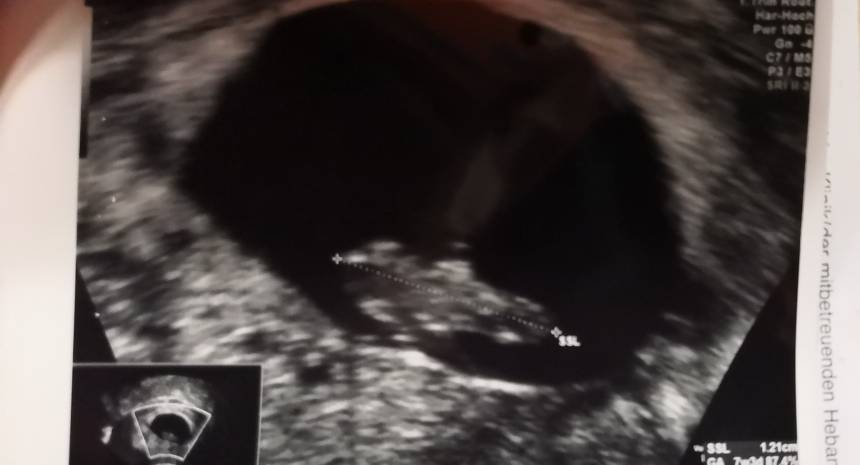

Wyszłam z gabinetu, dzidzius rosnie prawidlowo, puls prawie 170 czyli wszystko oki. Lekarz nie ma pojecia skad plamienie ale maluch ma się dobrze

No to super wieści [emoji16] oby więcej takichWyszłam z gabinetu, dzidzius rosnie prawidlowo, puls prawie 170 czyli wszystko oki. Lekarz nie ma pojecia skad plamienie ale maluch ma się dobrze![]()

Super cieszę sięWyszłam z gabinetu, dzidzius rosnie prawidlowo, puls prawie 170 czyli wszystko oki. Lekarz nie ma pojecia skad plamienie ale maluch ma się dobrze![]()